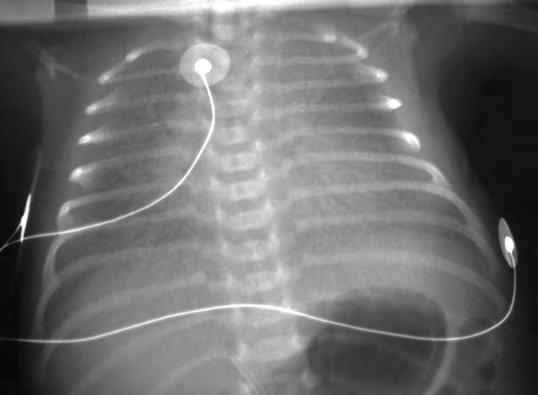

En un neonato pretérmino con dificultad respiratoria, el diagnóstico se basa en los antecedentes y, sobre todo, en el aspecto radiográfico de los pulmones, si bien la radiografía puede no reflejar la gravedad de la afectación pulmonar. La radiografía puede ser normal en los primeros momentos, pero progresivamente aparecen los cambios típicos, pero no patognomónicos de SDR: disminución del volumen pulmonar, opacificación difusa de los campos pulmonares con un moteado fino de aspecto de vidrio esmerilado y broncogramas aéreos. La imagen radiológica depende del ciclo respiratorio y del tipo de asistencia respiratoria recibida. Además, se debe valorar siempre la posible presencia de complicaciones, como enfisema intersticial, neumotórax o evolución hacia una displasia broncopulmonar (DBP). Puede aparecer cardiomegalia y aumento del flujo pulmonar por cortocircuito izquierda-derecha a nivel del ductus arterioso. La valoración de la expansión pulmonar es útil para ajustar los parámetros del ventilador.